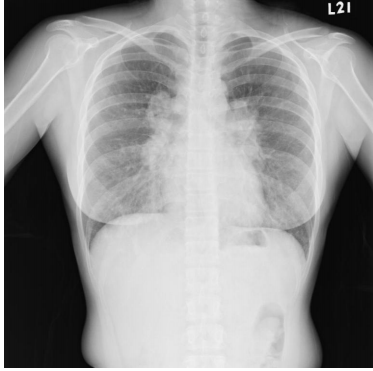

10. 35歲年輕女性,因健檢照了一張胸部X光,如下圖所示,此外,患者在小腿上有皮膚病兆,經診斷為結節性紅斑(erythema nodosum),請問下列哪些敘述正確 1. 需要轉介眼科醫師進行眼睛的評估 2. 該疾病的分期需要進一步使用電腦斷層進行分期 3. 所有患者均需接受治療 4. 該疾病容易造成多重器官侵犯 5. 所有患者的診斷均需要病理切片的檢查 (A) 1+3+4+5 (B) 1+2+4 (C) 1+4 (D) 2+3 (E) 2+4+5